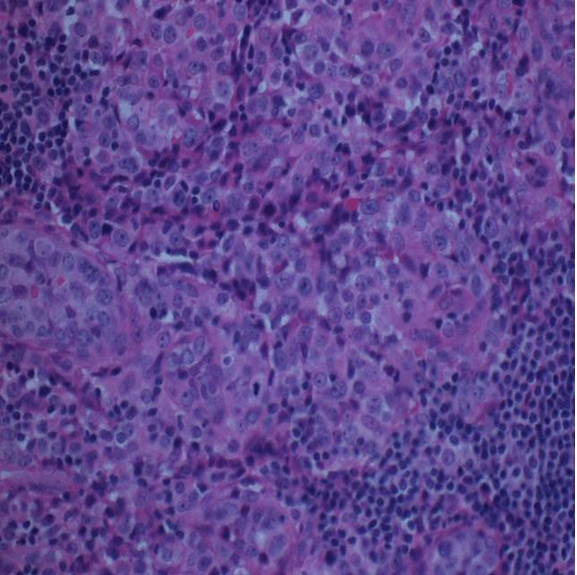

A 58-year-old male presented with a 10-month history of fever, weight loss and upper abdominal discomfort. He had intermittent fever, mostly at night, associated with night sweats. He had an unintentional weight loss of 20 lbs in the last six months. He had recently completed treatment for latent tuberculosis with six-month of isoniazid. On admission he was afebrile, and physical examination was significant for pallor and a palpable spleen. No lymph nodes were palpable. Laboratory data included hemoglobin 8.2 g/dL, white blood cell count 8.6x103/µL with a normal differential and platelet count 273x103/µL. Peripheral blood smear showed microcytosis and anisocytosis with no parasites identified on thick and thin smears. Sodium was 127 mEq/L. Other laboratory data included total bilirubin 0.7 mg/ dL, albumin 2.9 g/dL, AST 72 IU/L, ALT 24 IU/ L, LDH 1, 047 U/L, β2 microglobulin 4.2 mg/L, ESR 50 mm/hr and CRP 95.4 mg/L. Computed tomography scan of the chest, abdomen and pelvis showed homogenous splenomegaly with enlargement of the liver, without any intra-abdominal, pelvic, or retroperitoneal lymphadenopathy (Figure 1).

Figure 1: Computed tomography scan of abdomen showing hepatosplenomegaly.